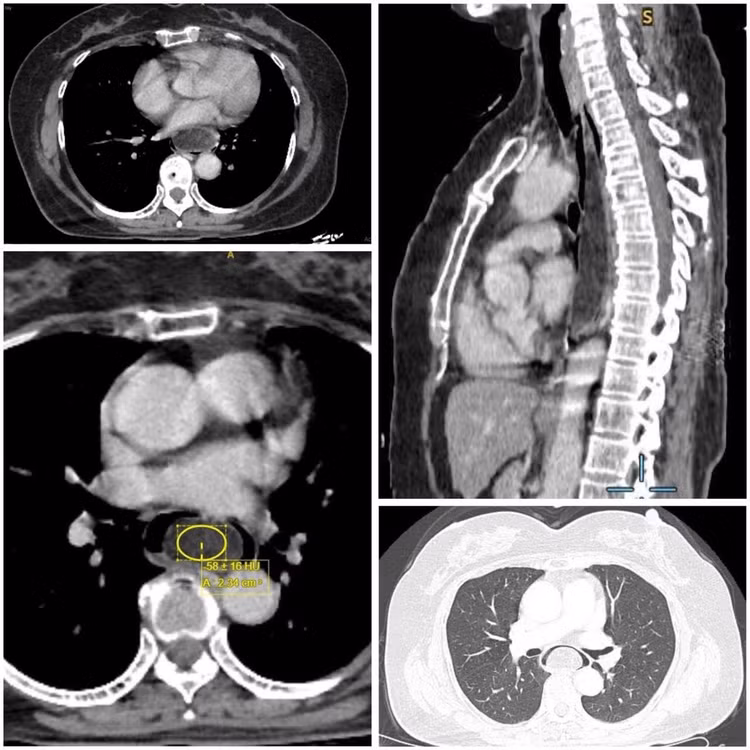

Sau quá trình khám lâm sàng, tìm hiểu diễn biến bệnh, thực hiện nội soi và siêu âm nội soi, các bác sĩ kết luận người bệnh có u mỡ thực quản dưới niêm mạc, kích thước 16 x 3,5 x 3 cm, đây là khối u có kích thước khủng, thông thường các khối u dưới niêm mạc đường tiêu hóa có kích thước thường nhỏ hơn 3cm.

u-mo-thuc-quan-1.jpg

Hình ảnh khu mỡ khủng trong thực quản dưới niêm mạc trên phim chụp - Ảnh BVCC